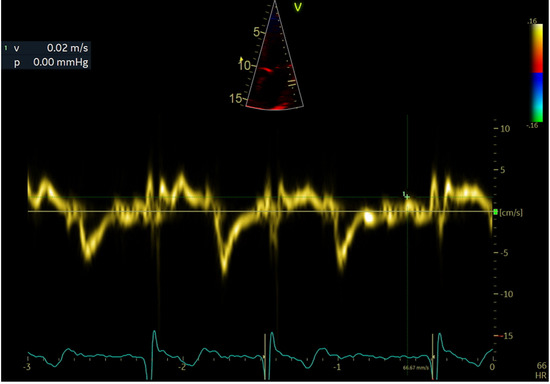

| LAWMV (cm/s) | 3.22 (1.07) | 3.69 (0.84) | 2.86 (1.09) | <0.001 |